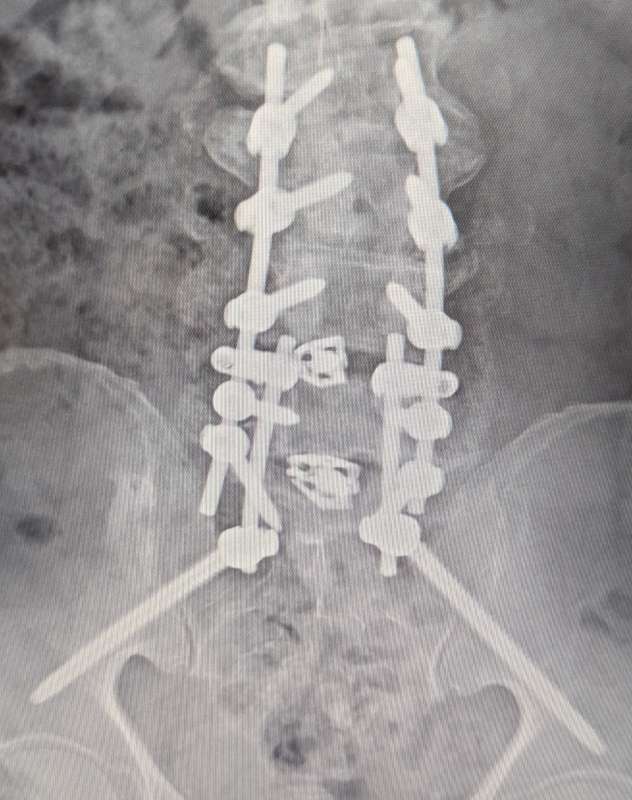

I just returned home from my first post surgery visit with my back surgeon.

Turns out he had to add a lot more hardware than originally anticipated.

I ended up with

14 screws

6 rods

2 cages

I'm 2 weeks out now and still sore, but it's getting better every day.

It going to be a long time before I know what my physical limitations will be..

Here's a couple pics or what my spine looks like as of this morning